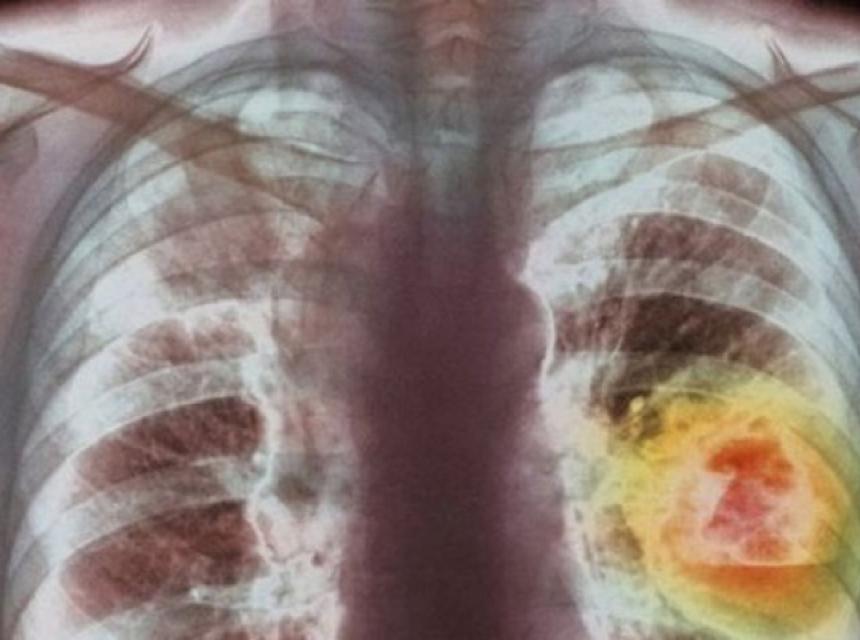

Studija je procijenila kako su se pacijenti oporavljali tri mjeseca nakon što su preboljeli covid-19. Istraživači su radili CT i test plućne funkcije kako bi vidjeli oštećeno plućno tkivo nakon oporavka od covida-19. Ustanovili su da se plućno tkivo nakon tri mjeseca dobro oporavlja.

Istraživači su primijetili da je preostala oštećenja plućnog tkiva ograničena, a to su najčešće viđali kod pacijenata koji su se liječili u jedinici intenzivne njege. U studiji se navode da su se nakon tri mjeseca od oporavka pacijenti najviše žalili na umor, otežano disanje i bolove u prsima.

“Obrasci koje vidimo kod ovih pacijenata pokazuju sličnosti s oporavkom nakon akutne upale pluća ili sindroma akutnog respiratornog distresa (ARDS), u kojem se tekućina nakuplja u plućima. Oporavak od ovih stanja obično traje dugo. Ohrabrujuće je vidjeti da pluća nakon infekcije covidom pokazuju ovu razinu oporavka”, kazao je pulmolog Bram van den Borst.